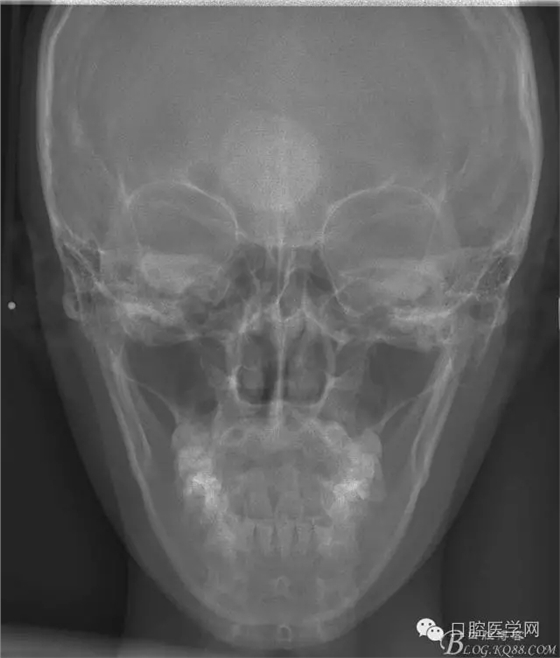

查:右側(cè)第二前磨牙第一乳磨牙恒尖牙頰側(cè)前庭溝隆起,捫有乒乓球感。曲斷及CT示:右側(cè)第二前磨牙第一乳磨牙恒尖牙根尖區(qū)有一囊腫,頰舌側(cè)骨板極薄,牙根無吸收,第二前磨牙牙根位于囊腫中,第一雙尖牙牙冠遠(yuǎn)中水平向阻生,牙冠位于囊腫中。經(jīng)協(xié)議:手術(shù)摘除創(chuàng)傷大,同意開創(chuàng)引流保守治療。

正畸查:替牙合。第一恒磨牙中性合。上牙弓尖圓型下牙弓方圓型。前牙覆合3度覆蓋7.5mm。下前牙咬到上舌側(cè)牙齦。上頜擁擠4.0mm,下頜擁擠

3.0mm。上頜稍前突下頜后縮,上下唇前突,上前牙覆蓋下唇,下唇外翻。面下三分之一過短,頦唇溝明顯,開唇露齒,頦饜窩明顯。顳下頜關(guān)節(jié)開閉口無彈響,無壓痛,開口型開口度正常。